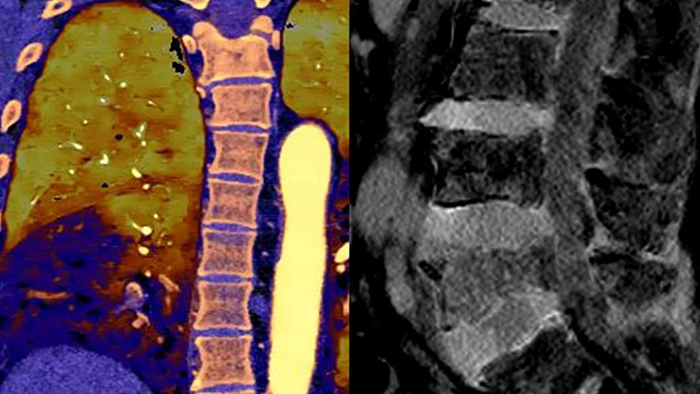

Грудная клетка, исследование на перикардиальный выпот

Брюшная полость/таз